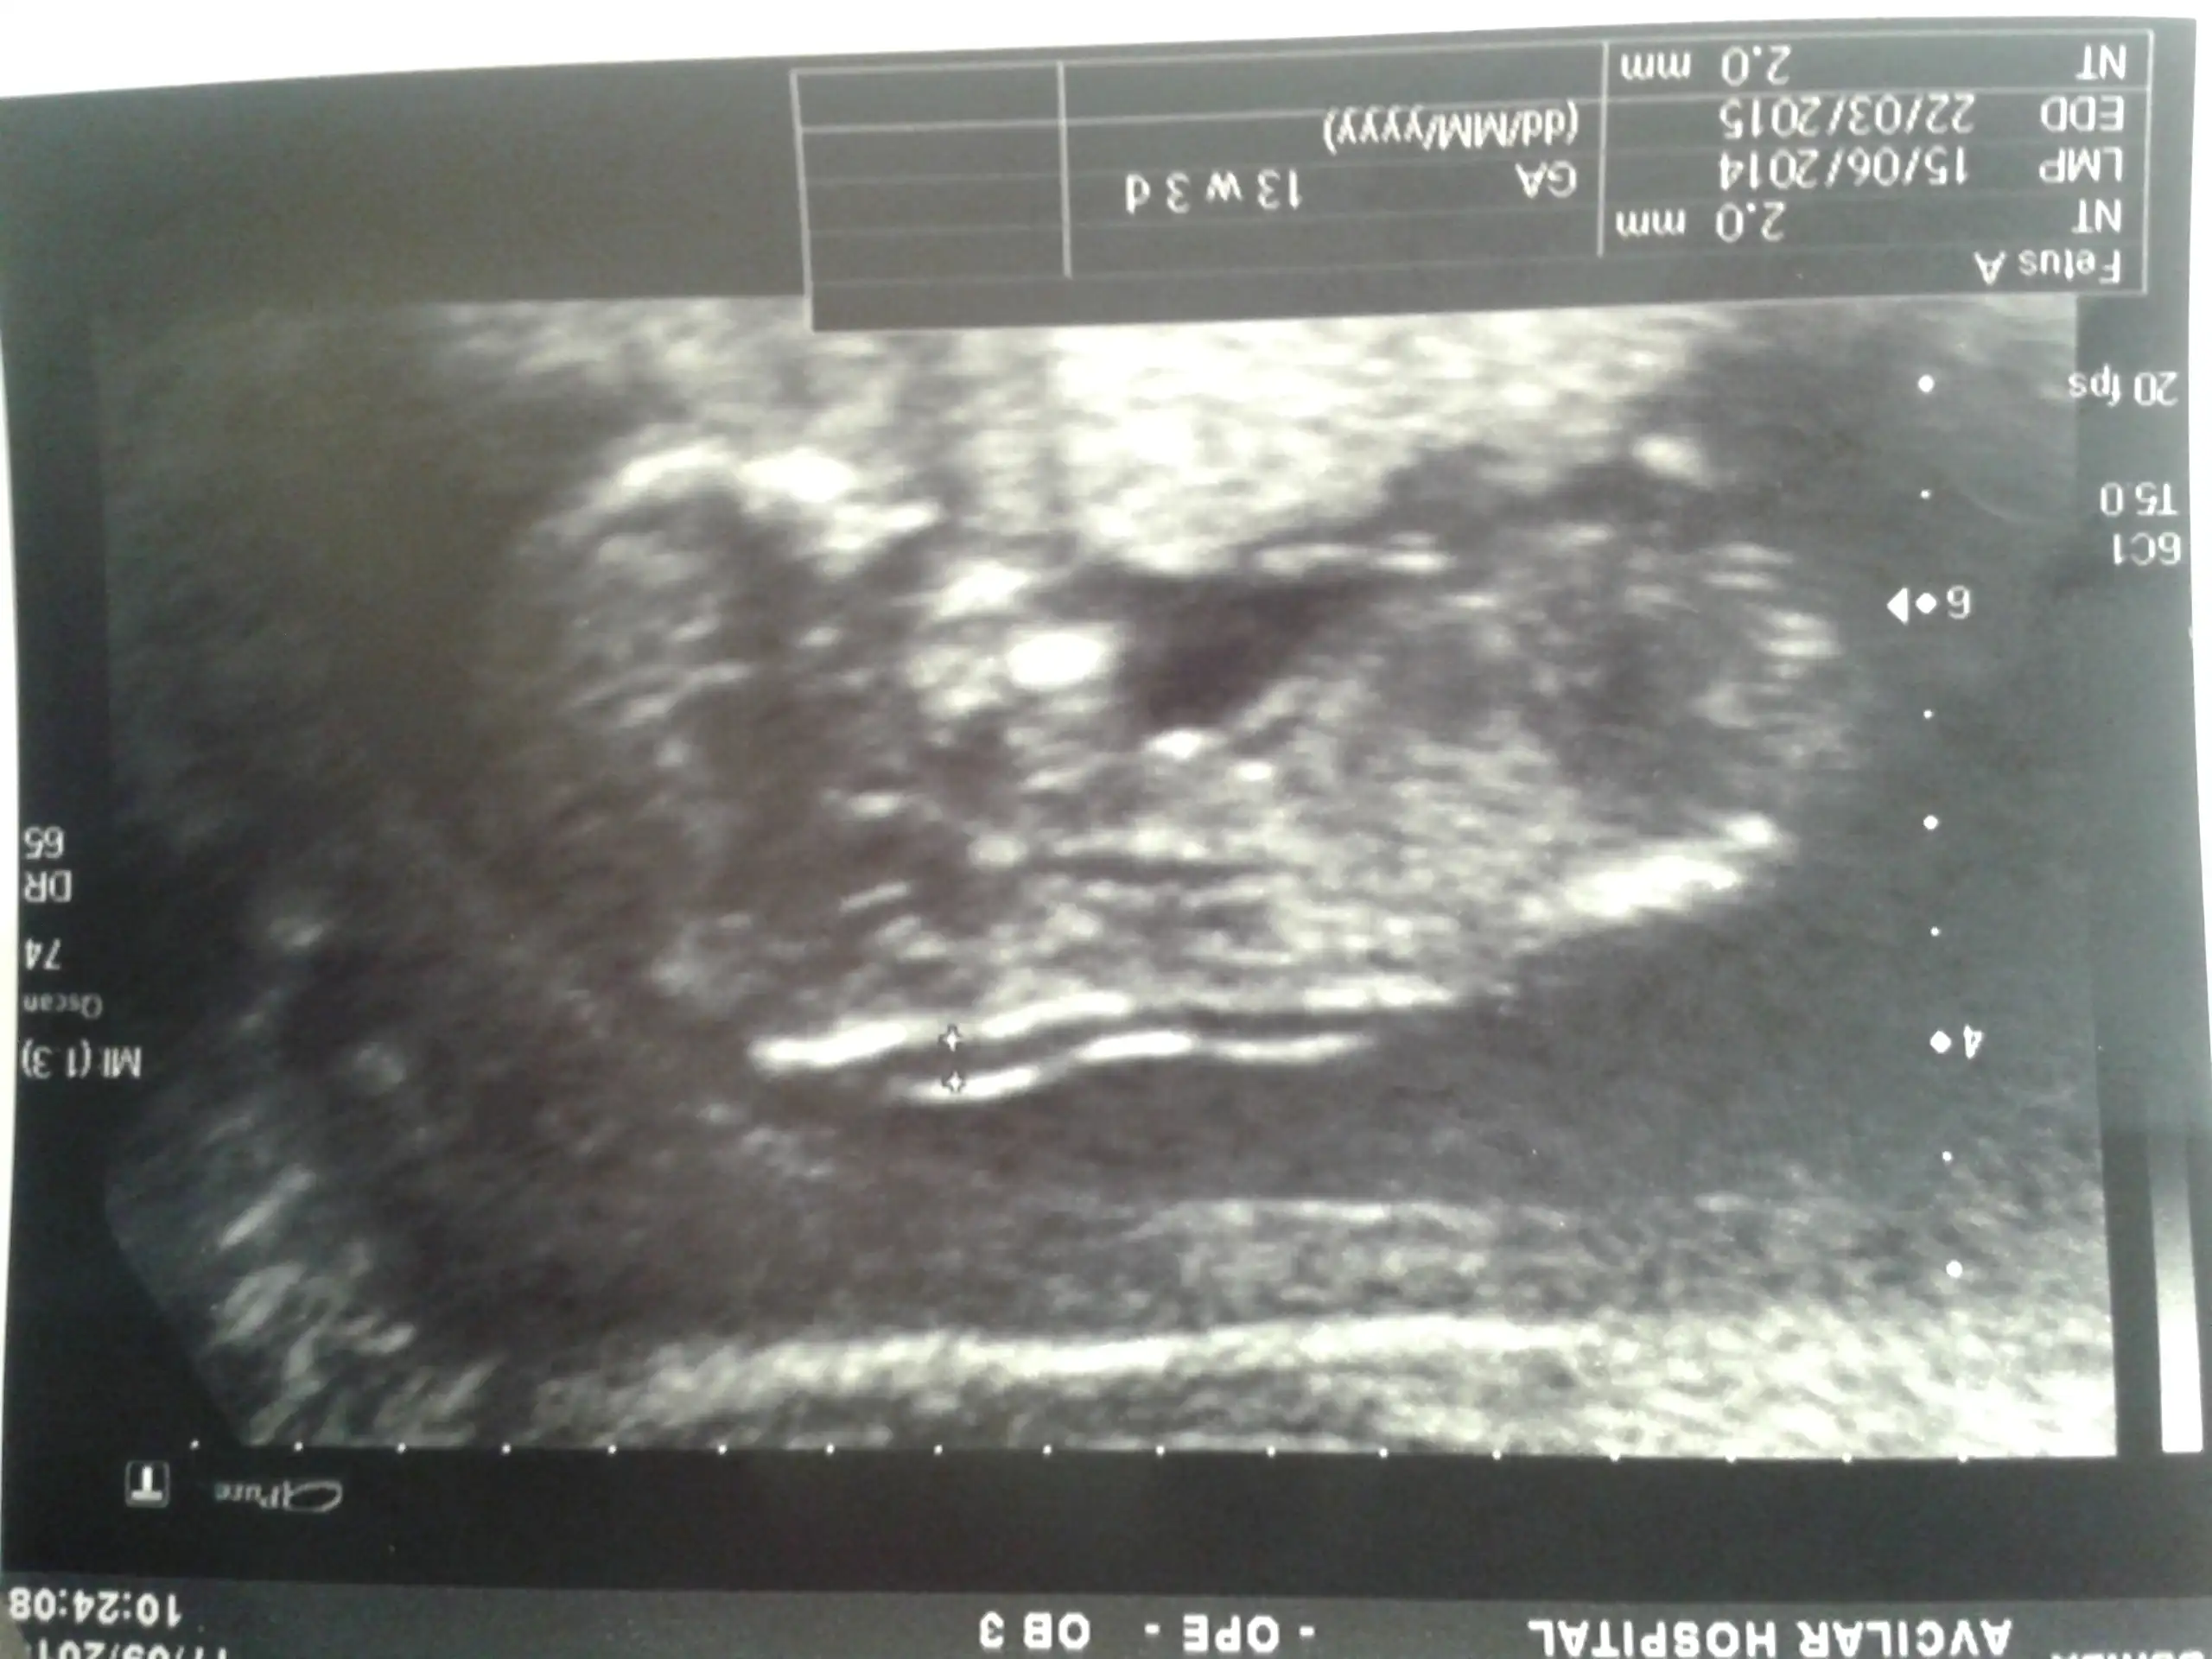

benimkine de bakar mısınız doktor erkek dedi ama daha 12+3 haftalık o yüzden tam kendimi kaptırmak istemiyorum